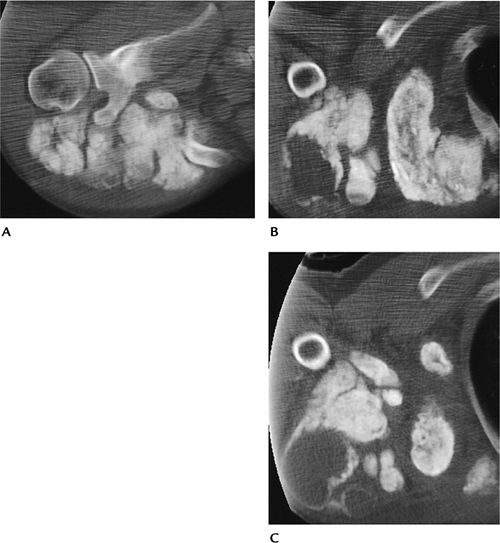

Radiographs or CT reveals periarticular

calcium masses, often forming multiple lobules. The hips, shoulders,

elbows, and ankles are most commonly involved. -

FIGURE 15-36 Tumoral calcinosis. CT images (A–C) of the shoulder demonstrate large loculated calcium masses.